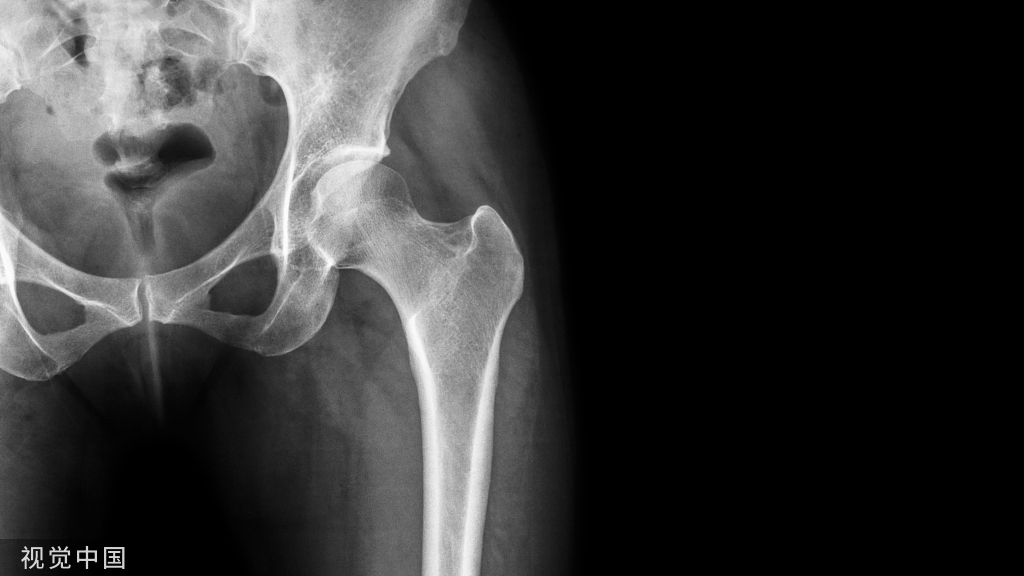

手术椎体的确定

X线片上往往不能判断脊柱骨折处于骨质愈合的哪个阶段多椎体的骨折可能发生于不同时期,并非每个被压缩椎体都是责任椎体,需要手术治疗MRI在判断骨折椎体是否愈合及选择手术椎体时起重要作用急性期或亚急性期(2-30天之间的骨折):T1WI呈低信号, T2WI呈高信号晚期(30天以后):T1WI和T2WI上表现等信号。

当椎体T1WI、T2WI无信号改变,即使X线片椎体有压缩改变,亦说明椎体骨折已愈合,椎体已处于稳定状态,为非责任椎体,可不予治疗。相反对于X线片椎体无明显压缩,但MRI有显著信号改变者应考虑为责任椎体,予以手术。